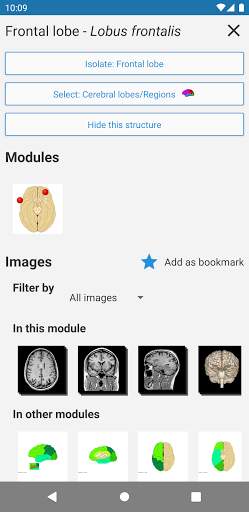

* تحسين عرض التفاصيل للأجزاء التشريحية لتسهيل التعرف عليها في صور الوحدات الحالية والوحدات الأخرى.

- يتميز وضع الدبابيس بسلوك جديد يسمح لك باتباع بنية تشريحية بسهولة أكبر

- ضمن عرض التفاصيل للبنية التشريحية ، يشير الدبوس الآن إلى البنية ذات الصلة في جميع الصور الحالية

انقر أيضًا مباشرة على الصورة للانتقال إلى الصورة المعروضة في تلك الوحدة

- "التصفية حسب" ، في عرض التفاصيل ، يمكنك الآن تصفية الصور التي تحتوي على الهيكل التشريعي حسب الطريقة

- "التصفية حسب" ، في عرض التفاصيل ، يمكنك الآن تصفية الصور التي تحتوي على الهيكل التشريعي حسب الطريقة